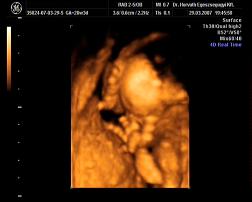

Mi meg megjöttünk az uh-ról, Ákosom nagyon szégyenlősvolt, már ami a kis arcát illeti, mert végig az arca előtt volt mindkétkeze, dörzsölte a szemét....néha profilból el lehetett kapni egy-egy pillanatot, szerintem gyönyörű...már olyan babás! Bezzeg a kukacát, azt mutogatta szorgosan! Meg megmutatta a kezeit, lábait, és hát néha a kis arcát is ki lehetett venni, de szemből teljesen most nem mutatta meg magát. De ami a legfontosabb, minden a legnagyobb rendben Vele, a gerince gyönyörű, gyomortelítődés szépen látható, vesék is szépek, koponya rendben....szóval minden okés, és ez a lényeg. Már 31O gramm a kis Drágám! Nagyon jó volt az egészvizsgálat, csak azt sajnálom, hogy nem sikerült képet készíteni Róla, pedig a doki mindent megtett...deDVD-t kaptunk, majd abból megpróbálok valamit kiügyeskedtetni Apával.

Apa "büszkesége" :D Kép

porsika